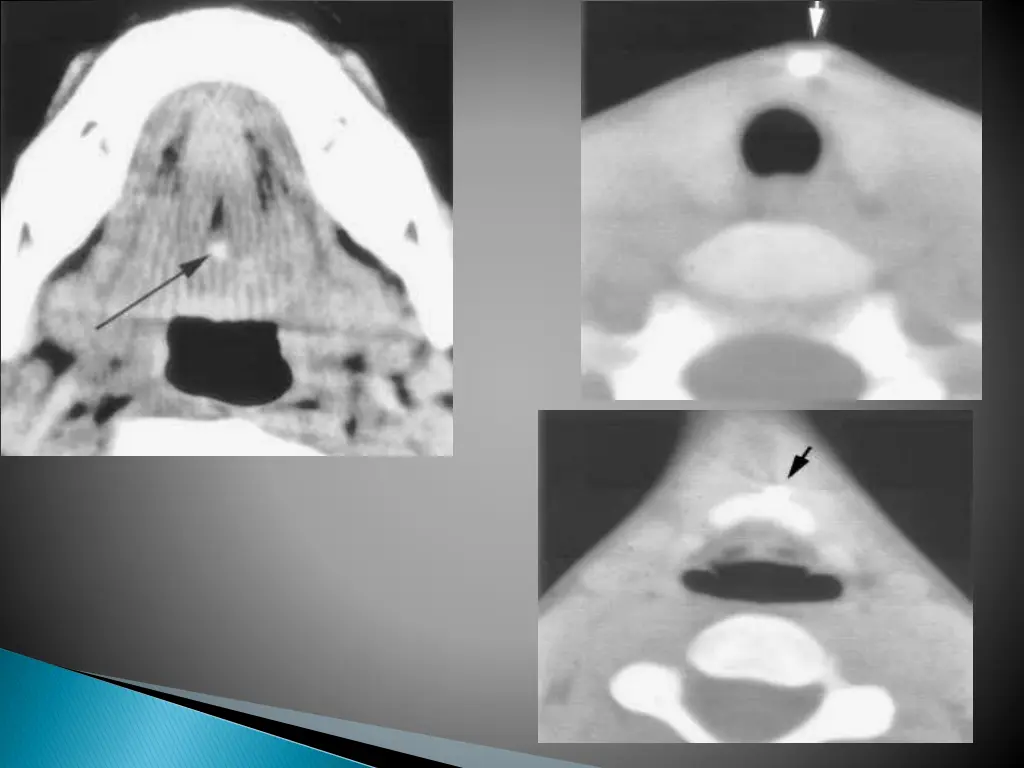

Smooth well circumscribed mass anywhere along the course of the duct. Thin walled, with peripheral rim enhancement on post contrast study. Homogenous attenuation (10-18HU). Increased attenuation suggest increased protein content and correlated with prior history of infection. Usually unilocular, occasionally septations+ Beaking of strap muscles over the surface of cyst.

CECT shows a cystic lesion in the right strap muscles.